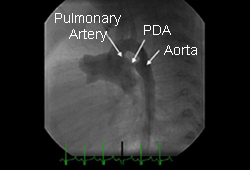

pda patent ductus sale